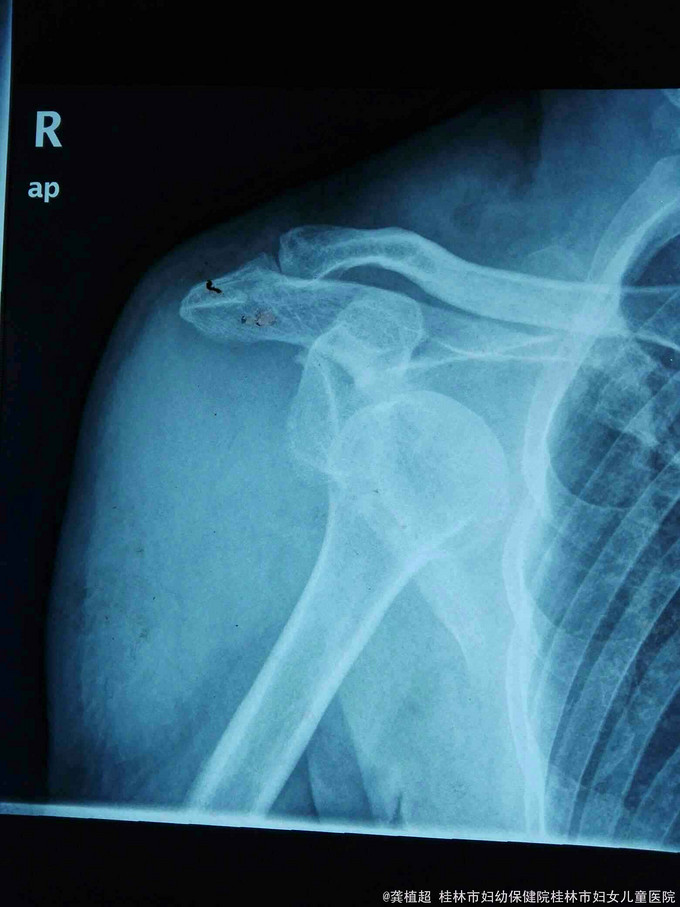

主诉:右肩外伤后疼痛、活动受限27天。 现病史:患者于2015年9月12日不慎跌倒右肩部先着地,右肩部剧烈疼痛、活动受限。肢体无麻木。在家自行外敷草药,症状无缓解。于2015年9月15日到我院门诊行X线检查提示右侧肩关节脱位。门诊予徒手复位术,疼痛明显缓解。术后复查X线示右肩关节复位良好,但患者诉右肩关节仍不能活动,同时伴有右小指麻木,第3、4指伸直受限。近3日上症加重遂来我院,行右上肢肌电图检查提示‘右侧臂丛神经损伤’,予收住院进一步诊治。饮食、睡眠、二便正常。

脊柱无明显畸形,各椎体无明显压、叩痛;右侧上臂近段前侧肿胀明显,右侧肩关节无压痛。右侧肩关节被动活动可,右侧三角肌肌力I级,其余右上肢肌群肌力约Iv级,右侧肩关节不能主动外展及前屈,右侧三角肌区皮肤及右手小指肌小鱼际肌部位浅感觉迟钝。肢端血运良好。

右侧臂丛神经损伤(腋神经、尺神经)